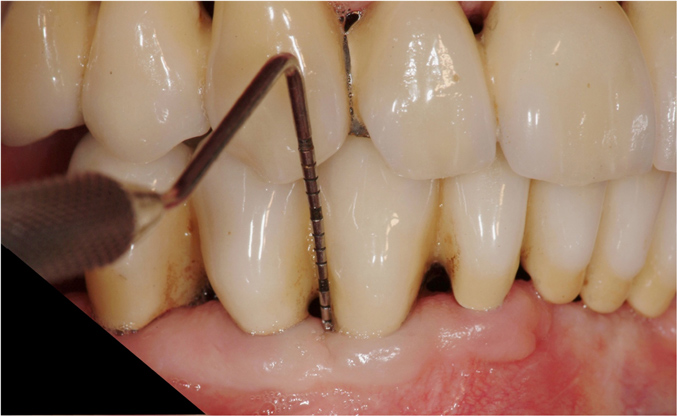

The teeth were prepared without violating the biologic width with intracrevicular preparations (Figure 3) and final impressions were made to establish master models, which were mounted using an electronic pantographic record. This record determined the condylar settings necessary to set an Arcon articulator. (There are now many articulators that are fully adjustable and easily programmable.) The master casts were made and mounted with a facebow to an Arcon articulator.

Figure 3 Tooth preparations were completed for full-coverage monolithic ceramic restorations.

Figure 3